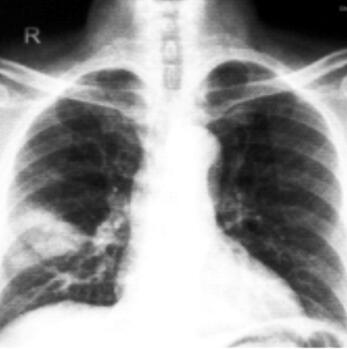

胸片:右肺下野外带斑片模糊影(图1)。

图1患者入院时的胸部X线片

5.血常规提示白细胞计数升高,血沉、降钙素原升高,血气提示低氧血症。胸片:右肺下野外带斑片模糊影。